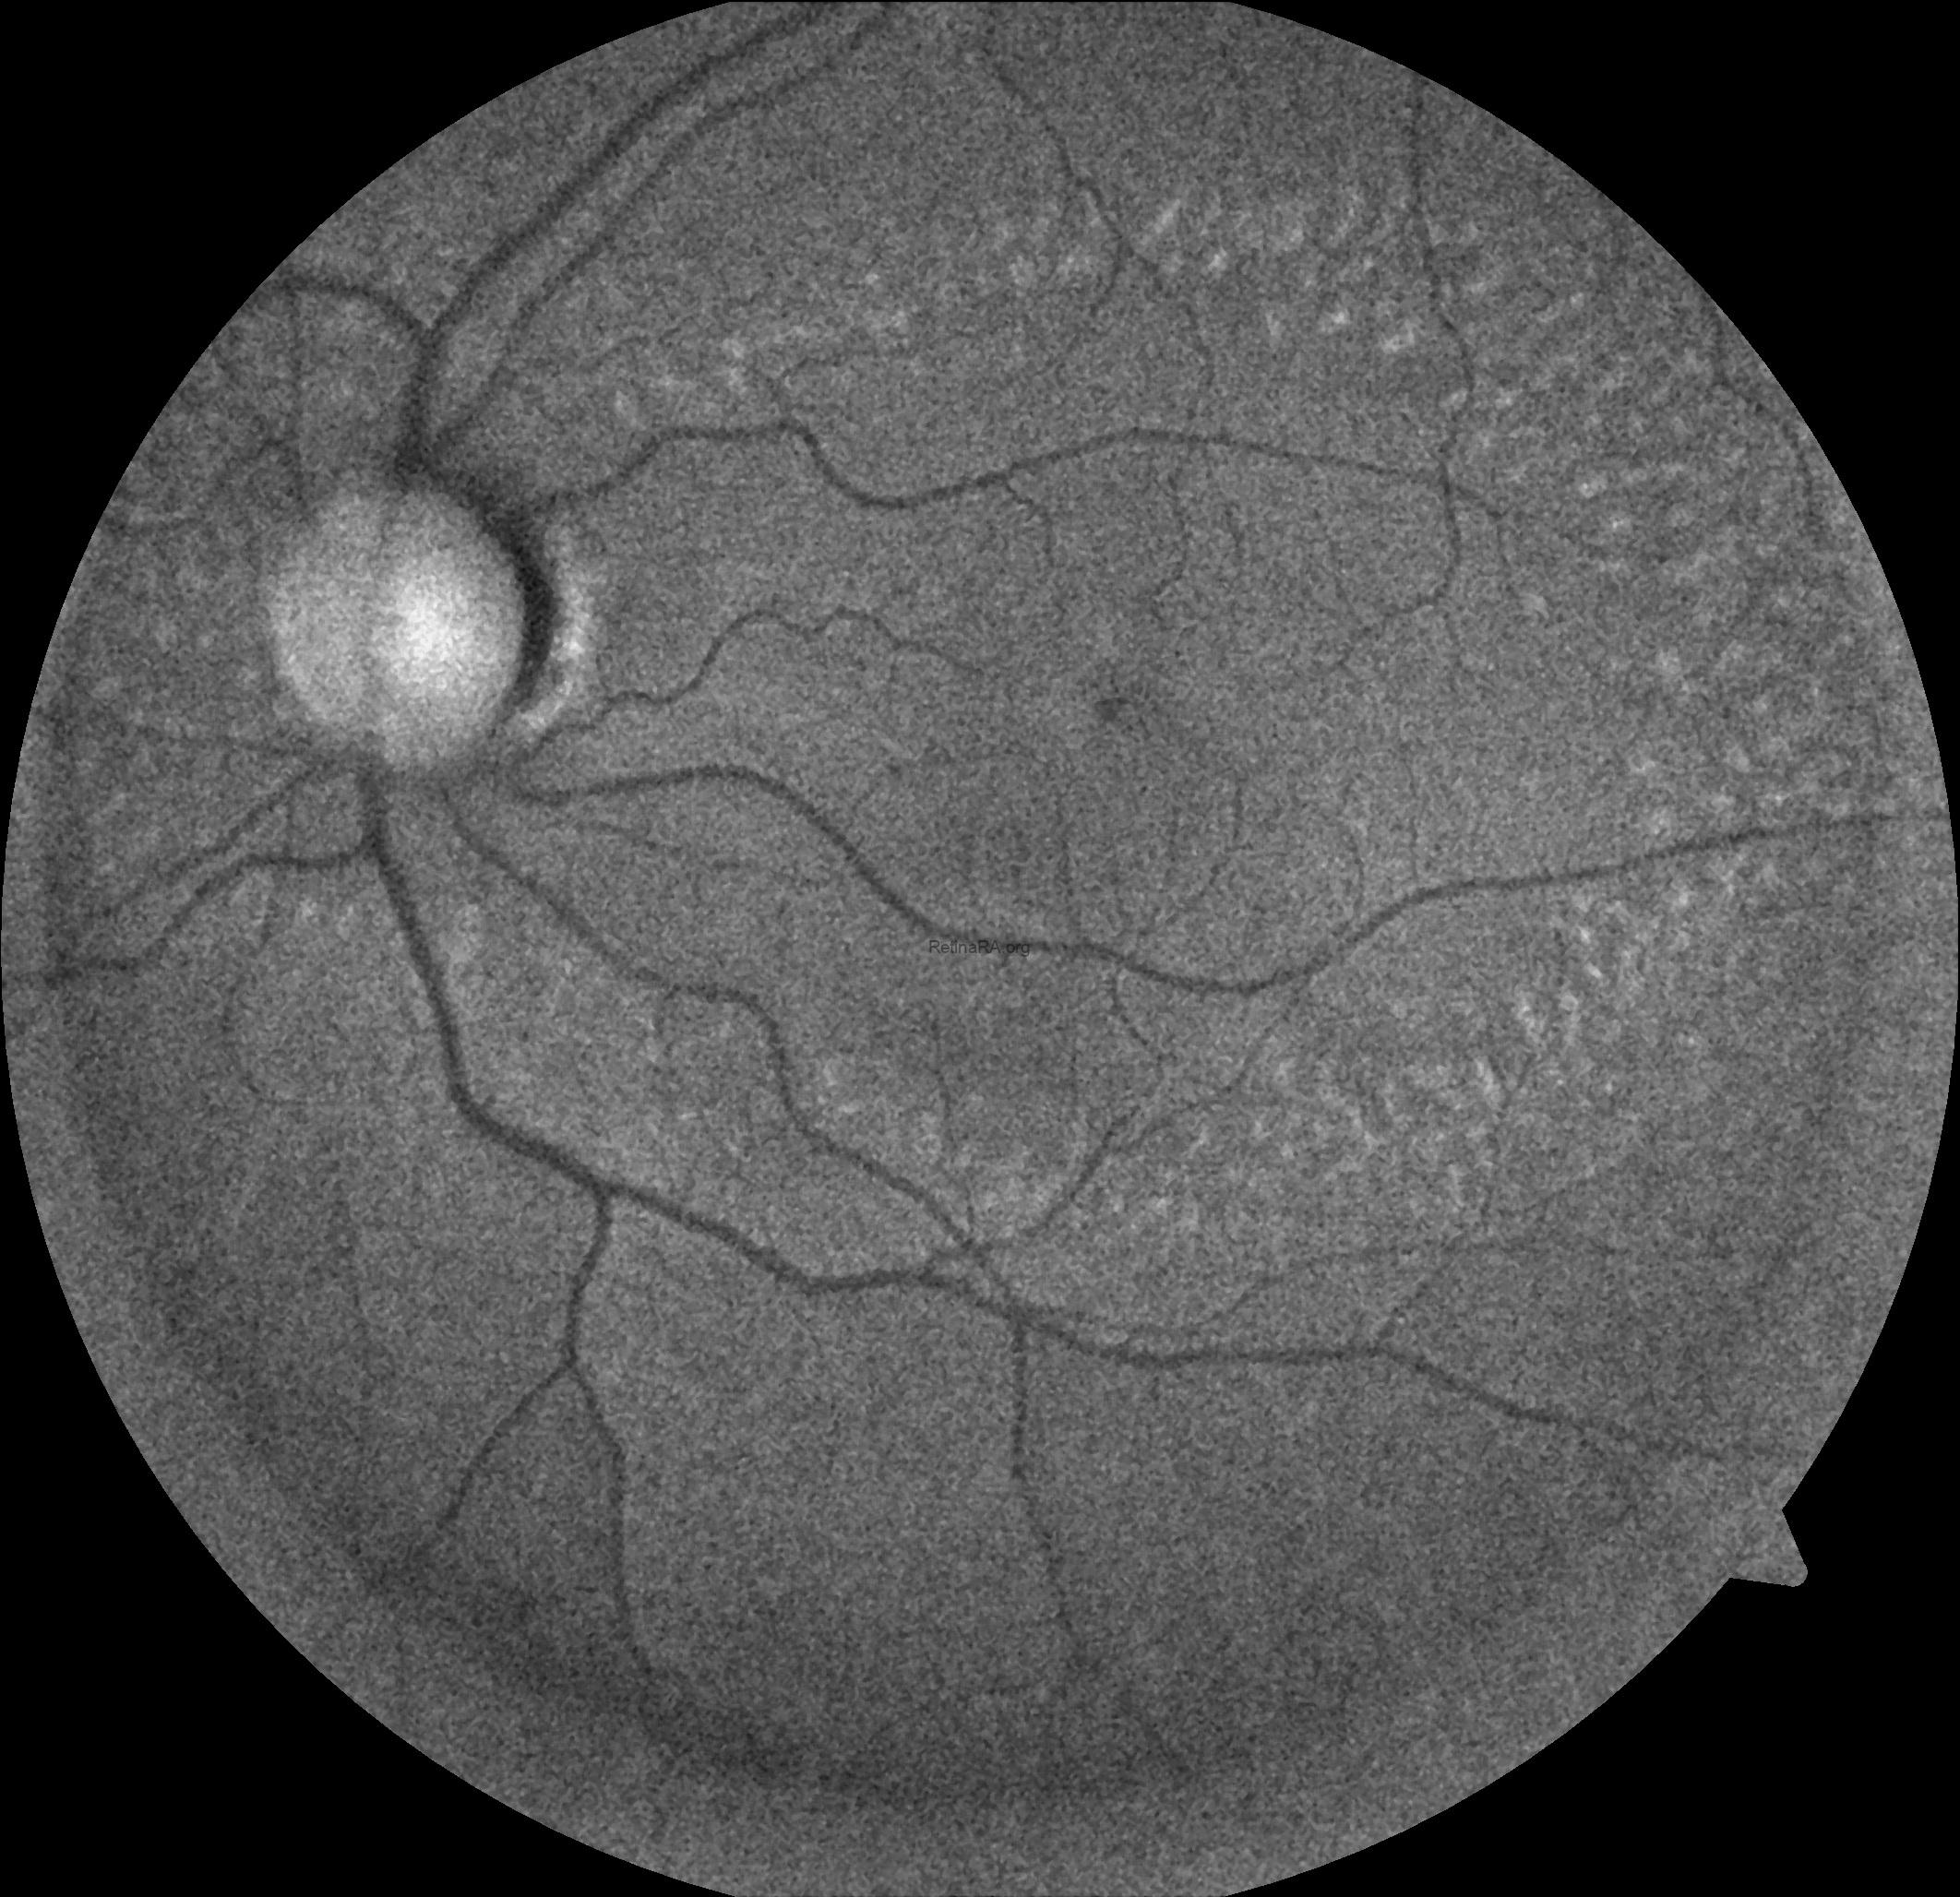

Ophthalmoscopic examination reveals scattered, discrete yellowish-white dots at the level of the retinal pigment epithelium, predominantly outside the macula. While these lesions are generally stable over time, partial regression has been documented in long-term follow-up. Histopathologically and functionally, these deposits are thought to represent accumulated retinoid intermediates, extending from the RPE–Bruch membrane complex into the outer retinal layers, including the outer nuclear layer.